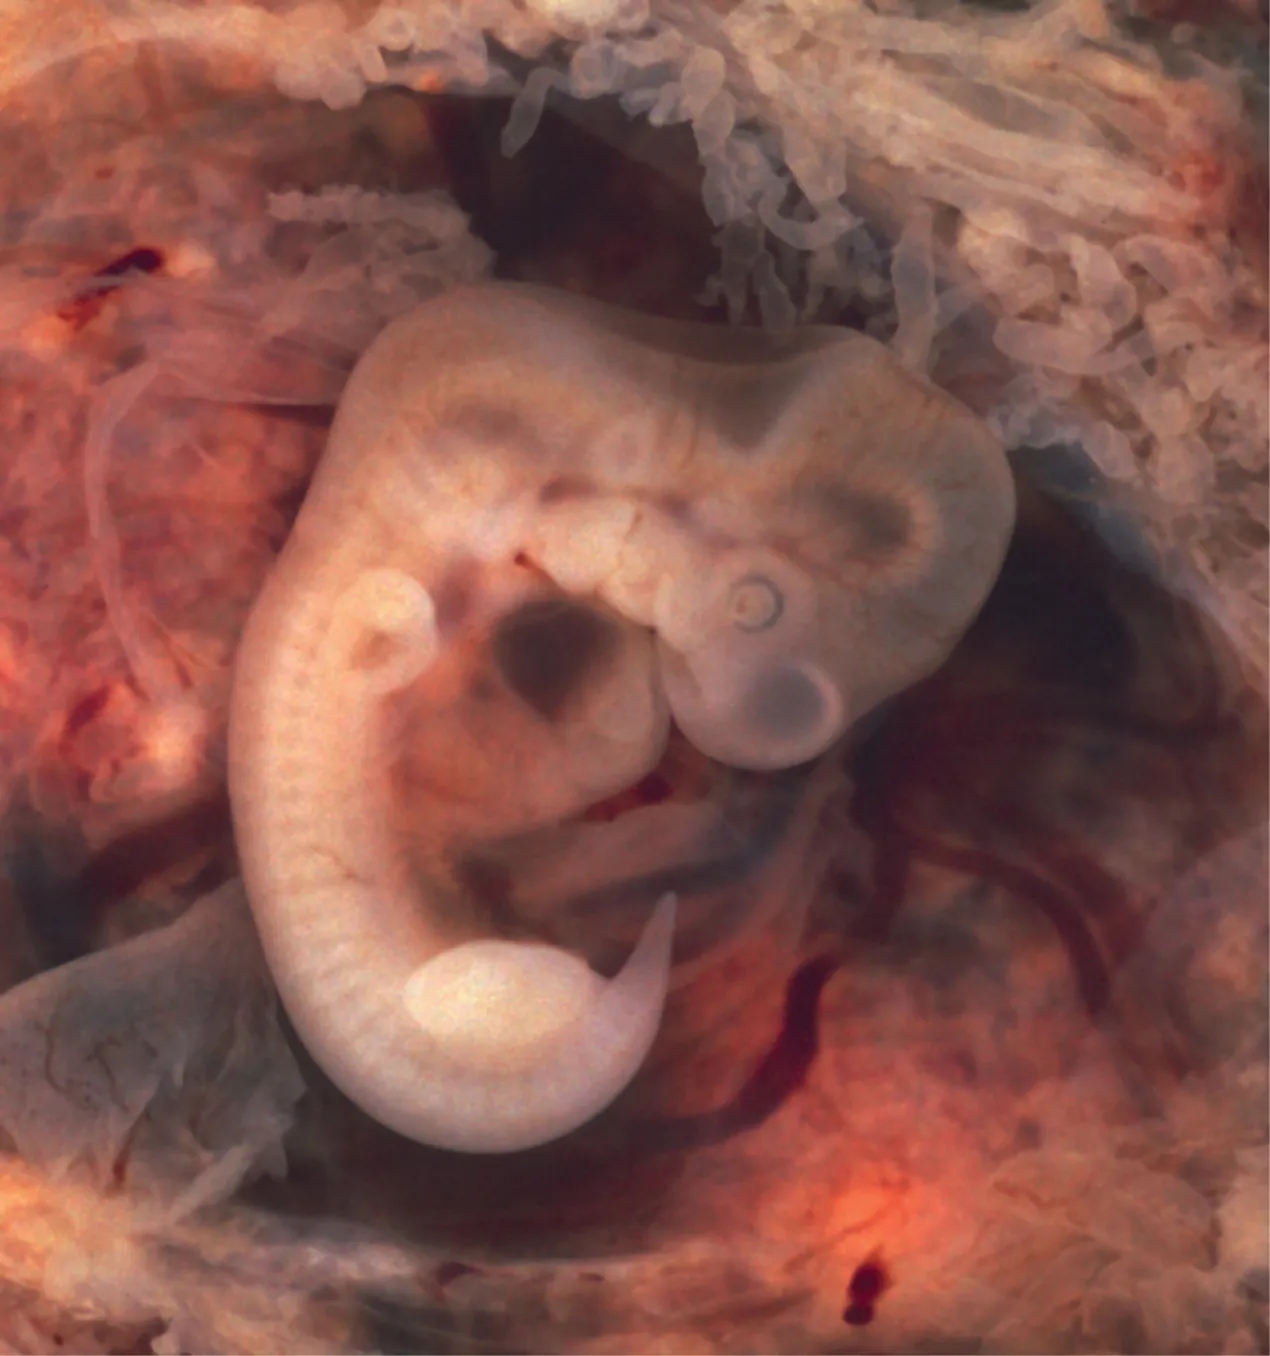

During the sixth week, uncontrolled fetal limb movements begin to occur. The gastrointestinal system develops too rapidly for the embryonic abdomen to accommodate it, and the intestines temporarily loop into the umbilical cord. Paddle-shaped hands and feet develop fingers and toes by the process of apoptosis (programmed cell death), which causes the tissues between the fingers to disintegrate. By week 7, the facial structure is more complex and includes nostrils, outer ears, and lenses (Figure 28.15). By the eighth week, the head is nearly as large as the rest of the embryo’s body, and all major brain structures are in place. The external genitalia are apparent, but at this point, male and female embryos are indistinguishable. Bone begins to replace cartilage in the embryonic skeleton through the process of ossification. By the end of the embryonic period, the embryo is approximately 3 cm (1.2 in) from crown to rump and weighs approximately 8 g (0.25 oz).

A photograph of an embryo derived from an ectopic pregnancy is shown.

Figure 28.15 Embryo at 7 Weeks An embryo at the end of 7 weeks of development is only 10 mm in length, but its developing eyes, limb buds, and tail are already visible. (This embryo was derived from an ectopic pregnancy.) (credit: Ed Uthman)